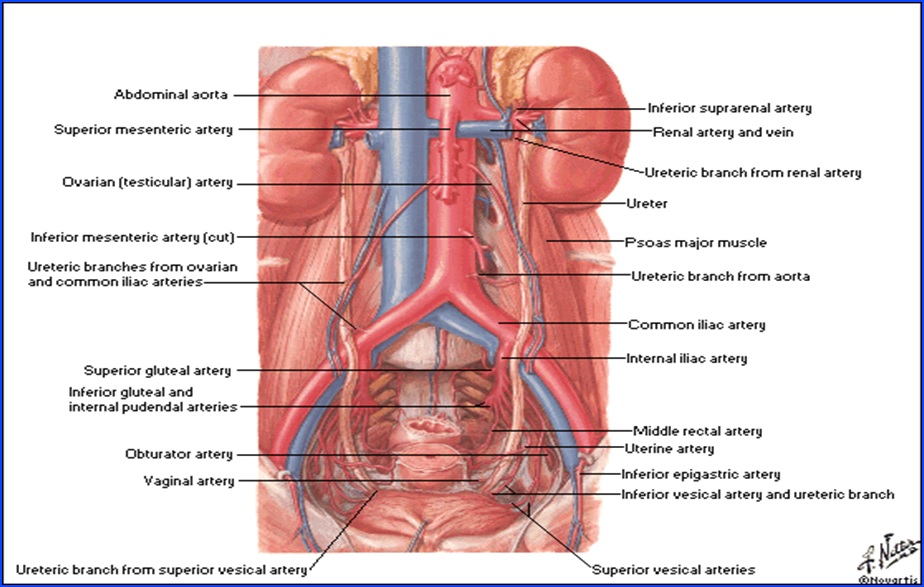

Rinichiul

Organ retroperitoneal, pereche şi simetric, cu formă asemănătoare bobului de fasole.

Dimensiuni şi greutate: depind de statura individului, vârstă, sex şi sunt în medie 12/6/3,5 cm; 140-170g.

Situaţie: de o parte şi alta a coloanei vertebrale, corespunzând vertebrelor T11-T12 superior şi L2-L3 inferior, de-a lungul marginii laterale a m. psoas. Prezenţa ficatului pe partea dreaptă face ca rinichiul drept să fie situat mai jos faţă de cel stâng.

Ureterul

- conduct intermediar între bazinet şi vezica urinară;

- 25-34 cm lungime, calibru inegal, cu strâmtori unde diametrul este de 2-4 mm şi “fuse” unde calibrul este de 5-10 mm;

- 3 stricturi anatomice:

- superioară - la nivelul joncţiunii pielo-ureterale;

- mijlocie - la incrucişarea cu vasele iliace;

- inferioară - la nivelul joncţiunii uretero-vezicale.

- traiect în ”S”

- după zonele pe care le străbate, se împarte în:

- Ureter abdominal

- Lombar

-Iliac - Ureter pelvin

- Parietal

- Vezical

- Ureter abdominal

Vascularizaţie:

Arterială:

- a. testiculară (r. din aorta abd.)

- a. deferenţială (r. din a. vezicală inf.)